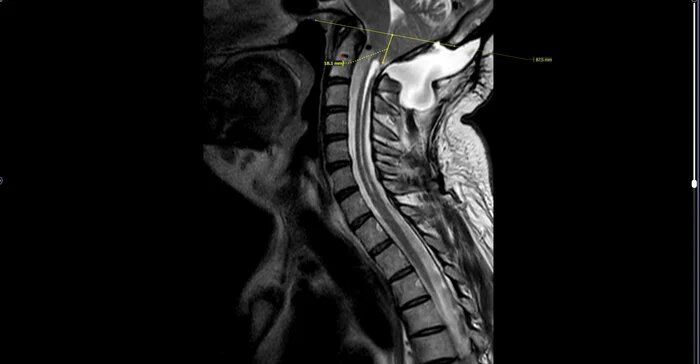

МРТ шейного отдела позвоночника пациента с жалобами на онемение правой стороны тела, потерю координации, общую слабость.

Определяется пролабирование миндалин мозжечка в большое затылочное отверстие до 18 мм.

Спинной мозг не деформирован, на уровне С1 - С7 отмечается расширение полости центрального канала до 3 мм, заполненное ликвором.

Ниже большого затылочного отверстия, на уровне С1 - С3 определяется отграниченное скопление ликвора размерами приблизительно 58х30х32 мм, исходящее из задней черепной ямки, наиболее вероятно менингоцеле( не типичная локализация, наиболее часто менингоцеле встречается в поясничном отделе позвоночника).

Заключение: МР- признаки аномалии Арнольда-Киари с образованием менингоцеле. Сирингомиелия спинного мозга шейного отдела.